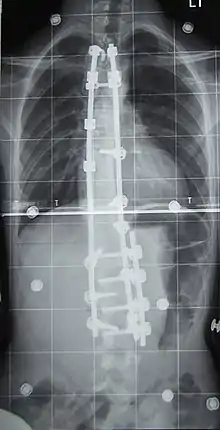

Surgery is usually recommended by orthopedists for curves with a high likelihood of progression (i.e., greater than 45–50° of magnitude), curves that would be cosmetically unacceptable as an adult, curves in people with spina bifida and cerebral palsy that interfere with sitting and care, and curves that affect physiological functions such as breathing.[99][100]

Surgery is indicated by the Society on Scoliosis Orthopaedic and Rehabilitation Treatment (SOSORT) at 45–50°[4] and by the Scoliosis Research Society (SRS) at a Cobb angle of 45°.[101] SOSORT uses the 45–50° threshold as a result of the well-documented, plus or minus 5° measurement error that can occur while measuring Cobb angles.[101]

Surgeons who are specialized in spine surgery perform surgery for scoliosis. To completely straighten a scoliotic spine is usually impossible, but for the most part, significant corrections are achieved.[102]

The two main types of surgery are:

- Anterior fusion: This surgical approach is through an incision at the side of the chest wall.

- Posterior fusion: This surgical approach is through an incision on the back and involves the use of metal instrumentation to correct the curve.

One or both of these surgical procedures may be needed. The surgery may be done in one or two stages and, on average, takes four to eight hours.